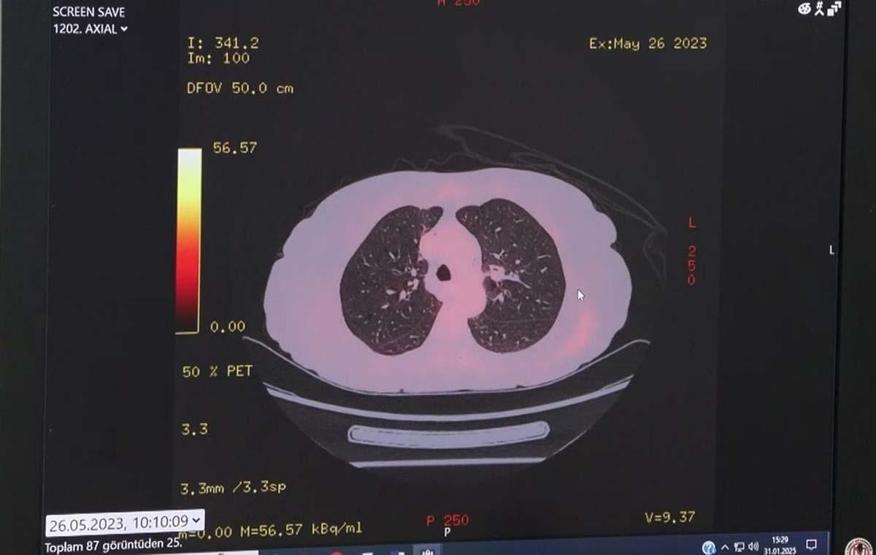

Gelişen teknolojiyle beraber kanser tedavisinde ortaya çıkan yeni yöntemlerden bahseden Prof. Dr. Çelik, sözlerini şöyle sürdürdü: “Kanser tedavisinde 1970’lerde kemoterapi ilaçları ile başlayan tedavi seçeneklerimiz 1990’lı yılların başından itibaren klinik araştırmalar sonucunda önce akıllı ilaçlar sonra immünoterapi dediğimiz tedavi yöntemleri ile gündemimize girmeye başladı. Bağışıklık sistemini harekete geçirerek tümöre karşı savaşmasını sağlayan bu immünoterapi ilaçları, kemoterapiye kıyasla daha az yan etki gösteriyor. Tüm bu ilaçlar sayesinde ileri evre akciğer kanserlerinde 5 yıllık yaşam oranı yüzde 5’ten yüzde 25’e kadar çıktı. Ancak immünoterapiyi sadece ileri evre kanserlerde değil, erken evre kanserlerde riskin azaltılması amacıyla da kullanabiliyoruz. Cerrahi öncesi ve sonrası hastalarda dahi bu yöntemi kullandığımız oluyor.”“Tümörün genetik yapısını analiz ederek, kişiye özel tedavi imkânı sunan akıllı ilaçlar, farklı kanser türlerinde etkili bir şekilde kullanılabiliyor. Kansere neden olan genlerin saptanma yöntemlerinde büyük ilerleme kaydedildi” diye konuşan Prof. Dr Çelik, “Bu sayede hangi hasta hangi ilaçtan daha çok fayda görür sorusunun cevabını daha kolay bulabiliyoruz. En sık küçük hücreli olmayan akciğer kanserinde kullandığımız bu tedaviler ile kanserin kaynak aldığı organdan bağımsız olarak genetik mutasyonuna göre tedavi dediğimiz ‘tümor agnostik’ tedavi seçeneklerimiz oluşmaya başladı” diye konuştu.Bunun yanında son yıllarda gündemimize hızlı bir giriş yapan ‘Antikor İlaç Konjugatları’ hakkında da bilgi veren Prof. Dr. Çelik, konuyla ilgili şunları anlattı: “Bu yeni tedavi yöntemi, tümör hücresini hedef alarak tümör hücresi içine yüksek dozda kemoterapi girmesini esas alıyor. Bu sayede tümör hücresi yok edilirken kemoterapinin diğer organlarda yaratabileceği yan etkiler de yaşanmıyor. Bugün meme, akciğer ve meme kanserlerinde kullandığımız bu yöntemin önümüzdeki günlerde çok daha yaygın kullanılacağının kanıtları ortaya çıkmaya başladı.”